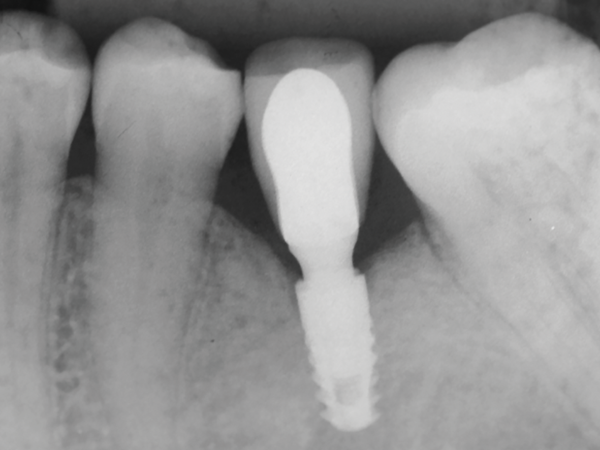

Neste contexto, em um recente estudo longitudinal de oito anos de acompanhamento1, observou-se que dos 44 pacientes e 202 implantes avaliados no período (Figura 1), o índice de sucesso foi de 96,6% e a incidência de peri-implantite (perda óssea radiográfica > 5 mm, profundidade de sondagem > 5 mm, sangramento a sondagem e/ou supuração) foi de 3%. A remodelação óssea peri-implantar foi de aproximadamente 1 mm após oito anos de avaliação (Figura 2). Entretanto, cumpre salientar que esta população apresentava um ótimo compliance, com retornos semestrais nos primeiros dois anos e anuais nos demais.

Figura 2 – Radiografia periapical de implante morse, sob função há oito anos. Note o mínimo remodelamento presente na região coronária.